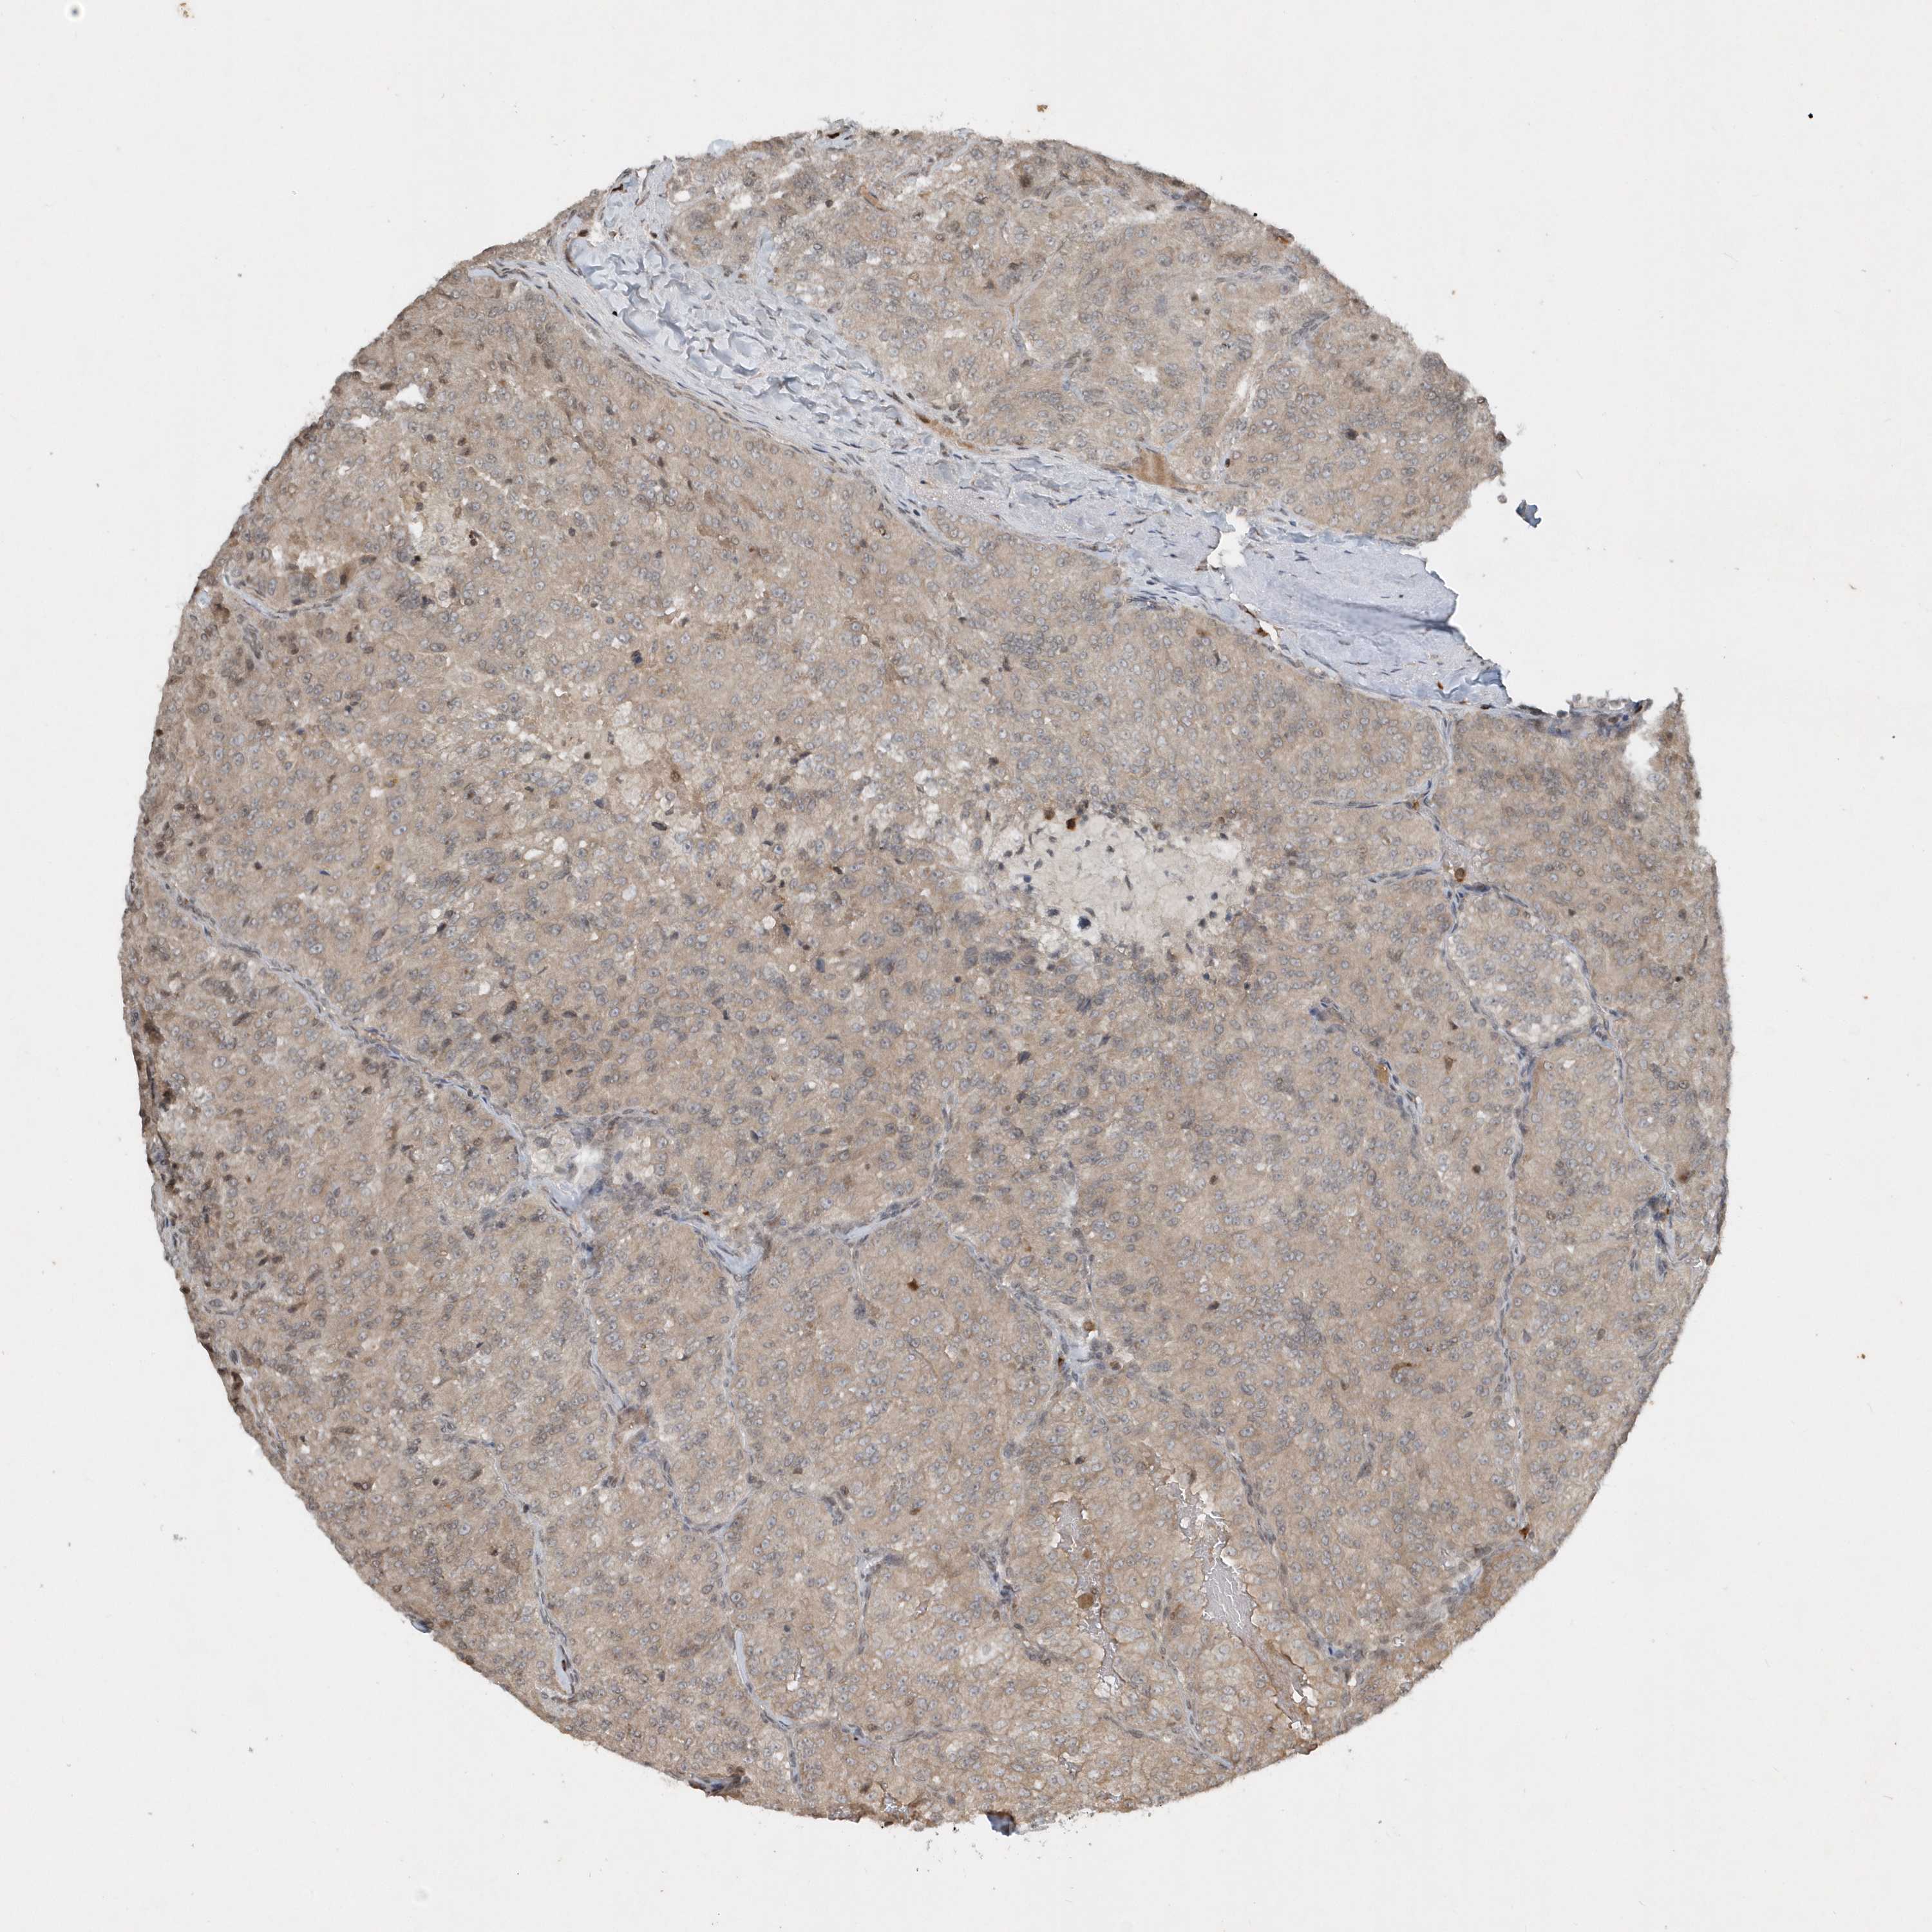

KIDNEY RENAL CLEAR CELL CARCINOMA (VALIDATION) - Interactive survival scatter ploti

The Survival Scatter plot shows the clinical status (i.e. dead or alive) for all individuals in the patient cohort, based on the same data that underlies the corresponding Kaplan-Meier plots. Patients that are alive at last time for follow-up are shown in blue and patients who have died during the study are shown in red.

The x-axis shows the expression levels (FPKM) of the investigated gene in the tumor tissue at the time of diagnosis. The y-axis shows the follow-up time after diagnosis (years). Both axes are complimented with kernel density curves demonstrating the data density over the axes. The top density plot shows the expression levels (FPKM) distribution among dead (red) and alive patients (blue). The right density plot shows the data density of the survived years of dead patients with high and low expression levels respectively, stratified using the cutoff indicated by the vertical dashed line through the Survival Scatter plot. This cutoff is automatically defined based on the FPKM cutoff that minimizes the p-score. The cutoff can be changed by dragging the vertical line or by entering a cutoff value in the square labeled "Current cut-off".

Under the Survival Scatter plot the p-score landscape (black curve; left axis) is shown together with dead median separation (red curve; right axis). Dead median separation is the difference in median mRNA expression between patients who have died with high and low expression, respectively. It is calculated as follows: median FPKM expression of dead patients with high expression - median FPKM expression of dead patients with low expression. This is intended to aid the user in visually exploring custom cutoffs and the associated p-scores and dead median separation.

Individual patient data is displayed and can be filtered by clicking on one or more of the category buttons on the top of the page. Categories describing expression level and patient information include: high, low, alive, dead, female, male and tumor stages. The scale of the x-axis can be toggled between linear and log-scale by clicking on the "x log" button. Mouse-over function shows TCGA ID, patient information and mRNA expression (FPKM) for each patient.

& Survival analysisi

Kaplan-Meier plots summarize results from analysis of correlation between mRNA expression level and patient survival. Patients were divided based on level of expression into one of the two groups "low" (under cut off) or "high" (over cut off). X-axis shows time for survival (years) and y-axis shows the probability of survival, where 1.0 corresponds to 100 percent.

EIF2B1 is not prognostic in Kidney Renal Clear Cell Carcinoma (validation)

Best expression cut offi

Based on the FPKM value of each gene, patients were classified into two groups and association between prognosis (survival) and gene expression (FPKM) was examined. The best expression cut-off refers the FPKM value that yields maximal difference with regard to survival between the two groups at the lowest log-rank P-value. Best expression cut-off was selected based on survival analysis .

When clicking on this number, the vertical dashed line indicating cut-off, the interactive survival plot, and the Kaplan-Meier curve will be adjusted to show results based on the best expression cut-off.

: 38.57

Median expressioni

Median expression refers to the median FPKM value calculated based on the gene expression (FPKM) data from all patients in this dataset. When clicking on this number, the vertical dashed line indicating cut-off, the interactive survival plot, and the Kaplan-Meier curve will be adjusted to show results based on the median expression.

: N/A

Median follow up timei

Median follow up time refers to the median time (years) after diagnosis with this type of cancer, based on clinical data from all patients in this dataset.

P scorei

Log-rank P value for Kaplan-Meier plot showing results from analysis of correlation between mRNA expression level and patient survival.

N/A

5-year survival highi

5-year survival for patients with higher expression than the expression cutoff.

For melanoma and glioma, 3-year survival is shown.

5-year survival lowi

5-year survival for patients with lower expression than the expression cutoff.

TCGA RNA samplesi

RNA-seq data is reported as average FPKM (number Fragments Per Kilobase of exon per Million reads), generated by the The Cancer Genome Atlas (TCGA) .

Normal distribution across the dataset is visualized with box plots, shown as median and 25th and 75th percentiles. Points are displayed as outliers if they are above or below 1.5 times the interquartile range. FPKM values of the individual samples are presented next to the box plot.

Average pTPM 41.7

Number of samples 100